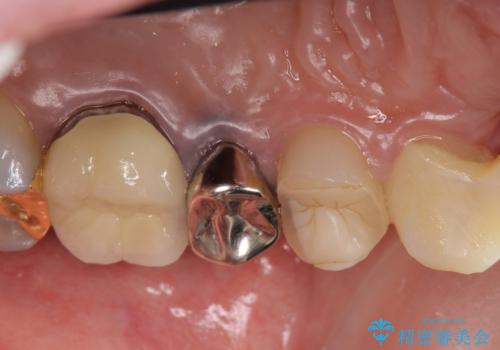

左上4、5番目の歯は根尖病変を認めたため再根管治療を行い、オールセラミッククラウンによる補綴を行いました。

なお左上4に関しては縁下歯質を改善するため、歯冠挺出を行っております。

歯冠延長術について

歯冠長延長術とは歯肉弁根尖側移動術とも言い、歯の高さが低くクラウン(被せ物)による治療が難しい場合に、歯茎を歯根方向に下げることで歯の高さを確保する手術です。歯の高さが十分にあることで、外れにくいしっかりとしたクラウンを被せることができます。